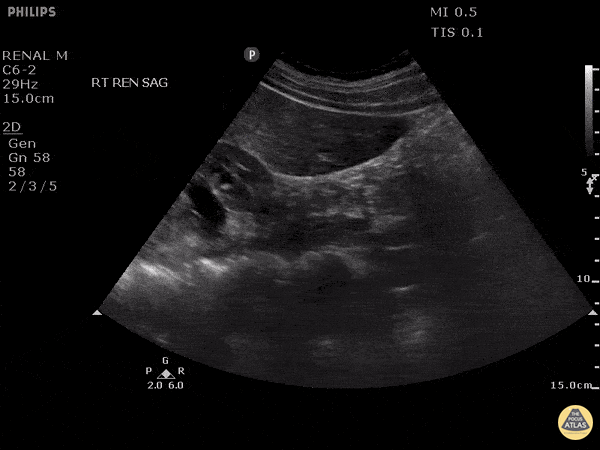

Ultrasound clip demonstrating both cholelithiasis as well as obstructing stone in the ureter! Image courtesy of Robert Jones DO, FACEP @RJonesSonoEM Director, Emergency Ultrasound; MetroHealth Medical Center; Professor, Case Western Reserve Medical School, Cleveland, OH View his original post here.